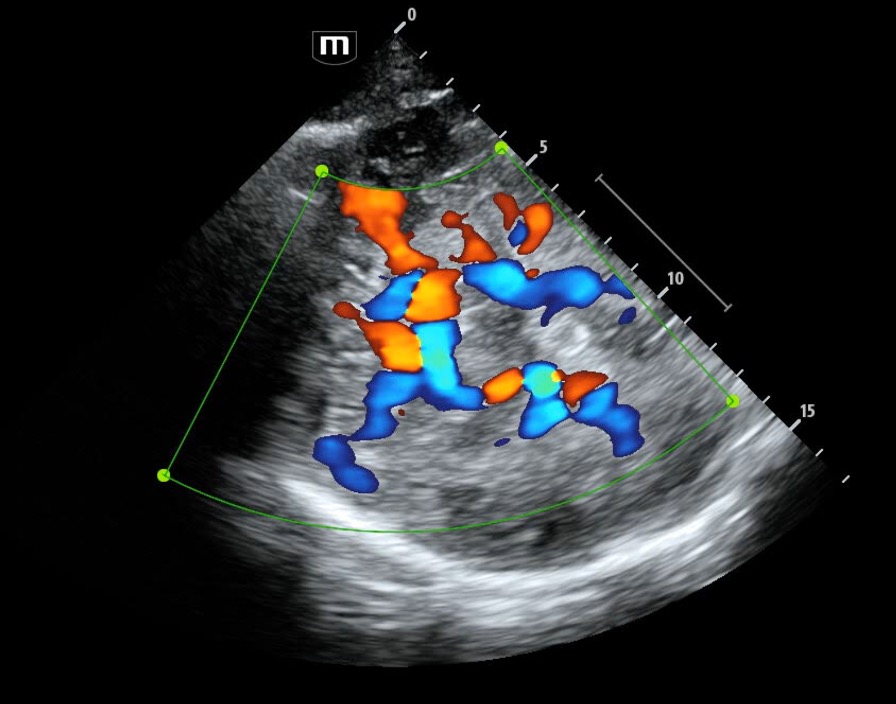

Pulmonary embolism (PE) represents a significant cause of preventable death among critically ill patients, with the immediate diagnosis impaired by the presence of hemodynamic compromise and lim...

Is that a clot or vegetation? #MedTwitter #Cardiology #echofirst @pocusmeded @WINFOCUS @Echo_Masters @Crit_Care @POCUSJournal @ICS_updates